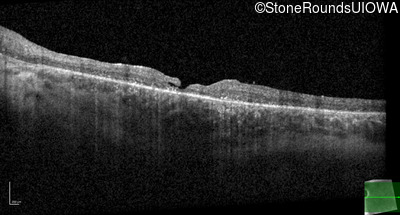

Optical Coherence Tomography - Left - 20/50

Exemplar / OCT Stack

OCT Stack